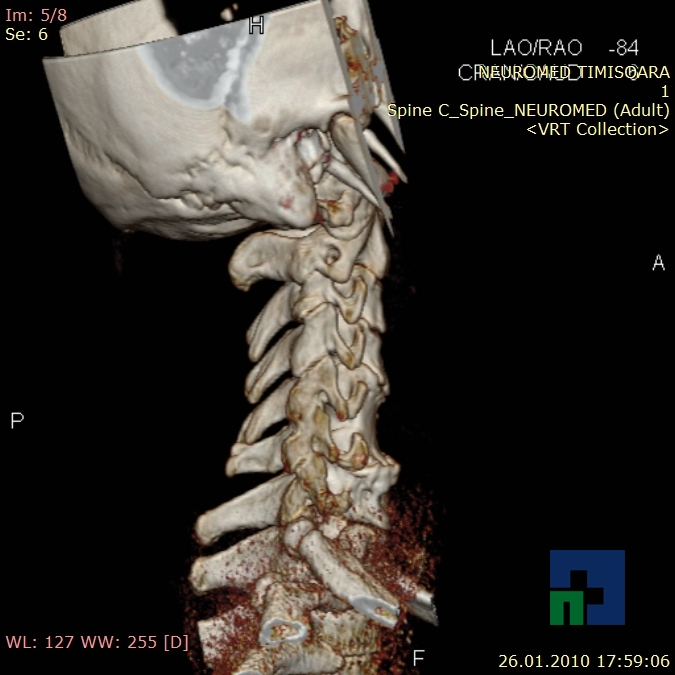

- Diagnosticul fracturilor:

- Unice

- Multiple

- Cu înfundare

- Complexe cranio-sinusale

- Complexe cranio-etmoidale

- Complexe cranio-orbitare

- Complexe cranio-faciale